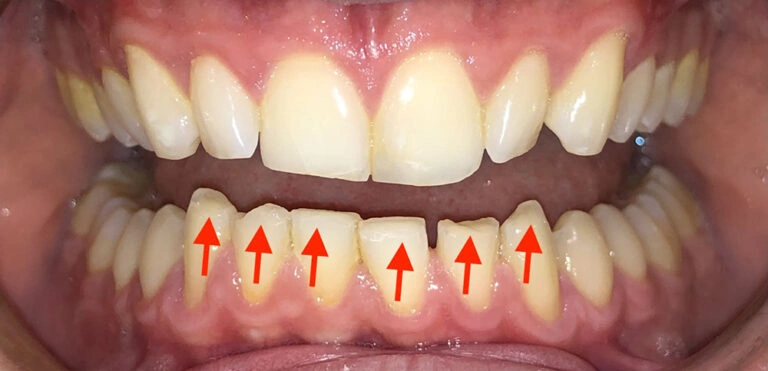

3. Localized Gum Recession: When the Gums Aren’t Protecting the Teeth

The third issue parents need to be aware of is localized recession. This occurs when the gums and bone no longer cover the teeth properly, exposing the roots.

While this might seem like a minor concern, it can actually lead to sensitivity, pain, and even tooth loss.

Visual Example:

Patient Example (young child)